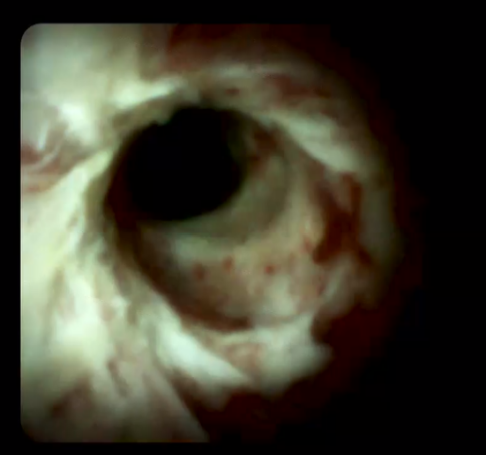

另外,經(jīng)口膽道子鏡光纖直視系統(tǒng)(SPYGLASS)是一種電子膽道子鏡,可通過(guò)十二指腸鏡到達(dá)膽管或胰管內(nèi),對(duì)病變進(jìn)行直視觀察,高清高分辨率顯示病變、并精準(zhǔn)指導(dǎo)活檢,對(duì)于膽胰管狹窄的診斷治療具有重要意義。

259842c0b1ad45318354e54fe46ec3e0.Png   a002b78cca244f27bc594941e601792b.Png

經(jīng)口膽道鏡下膽管組織活檢